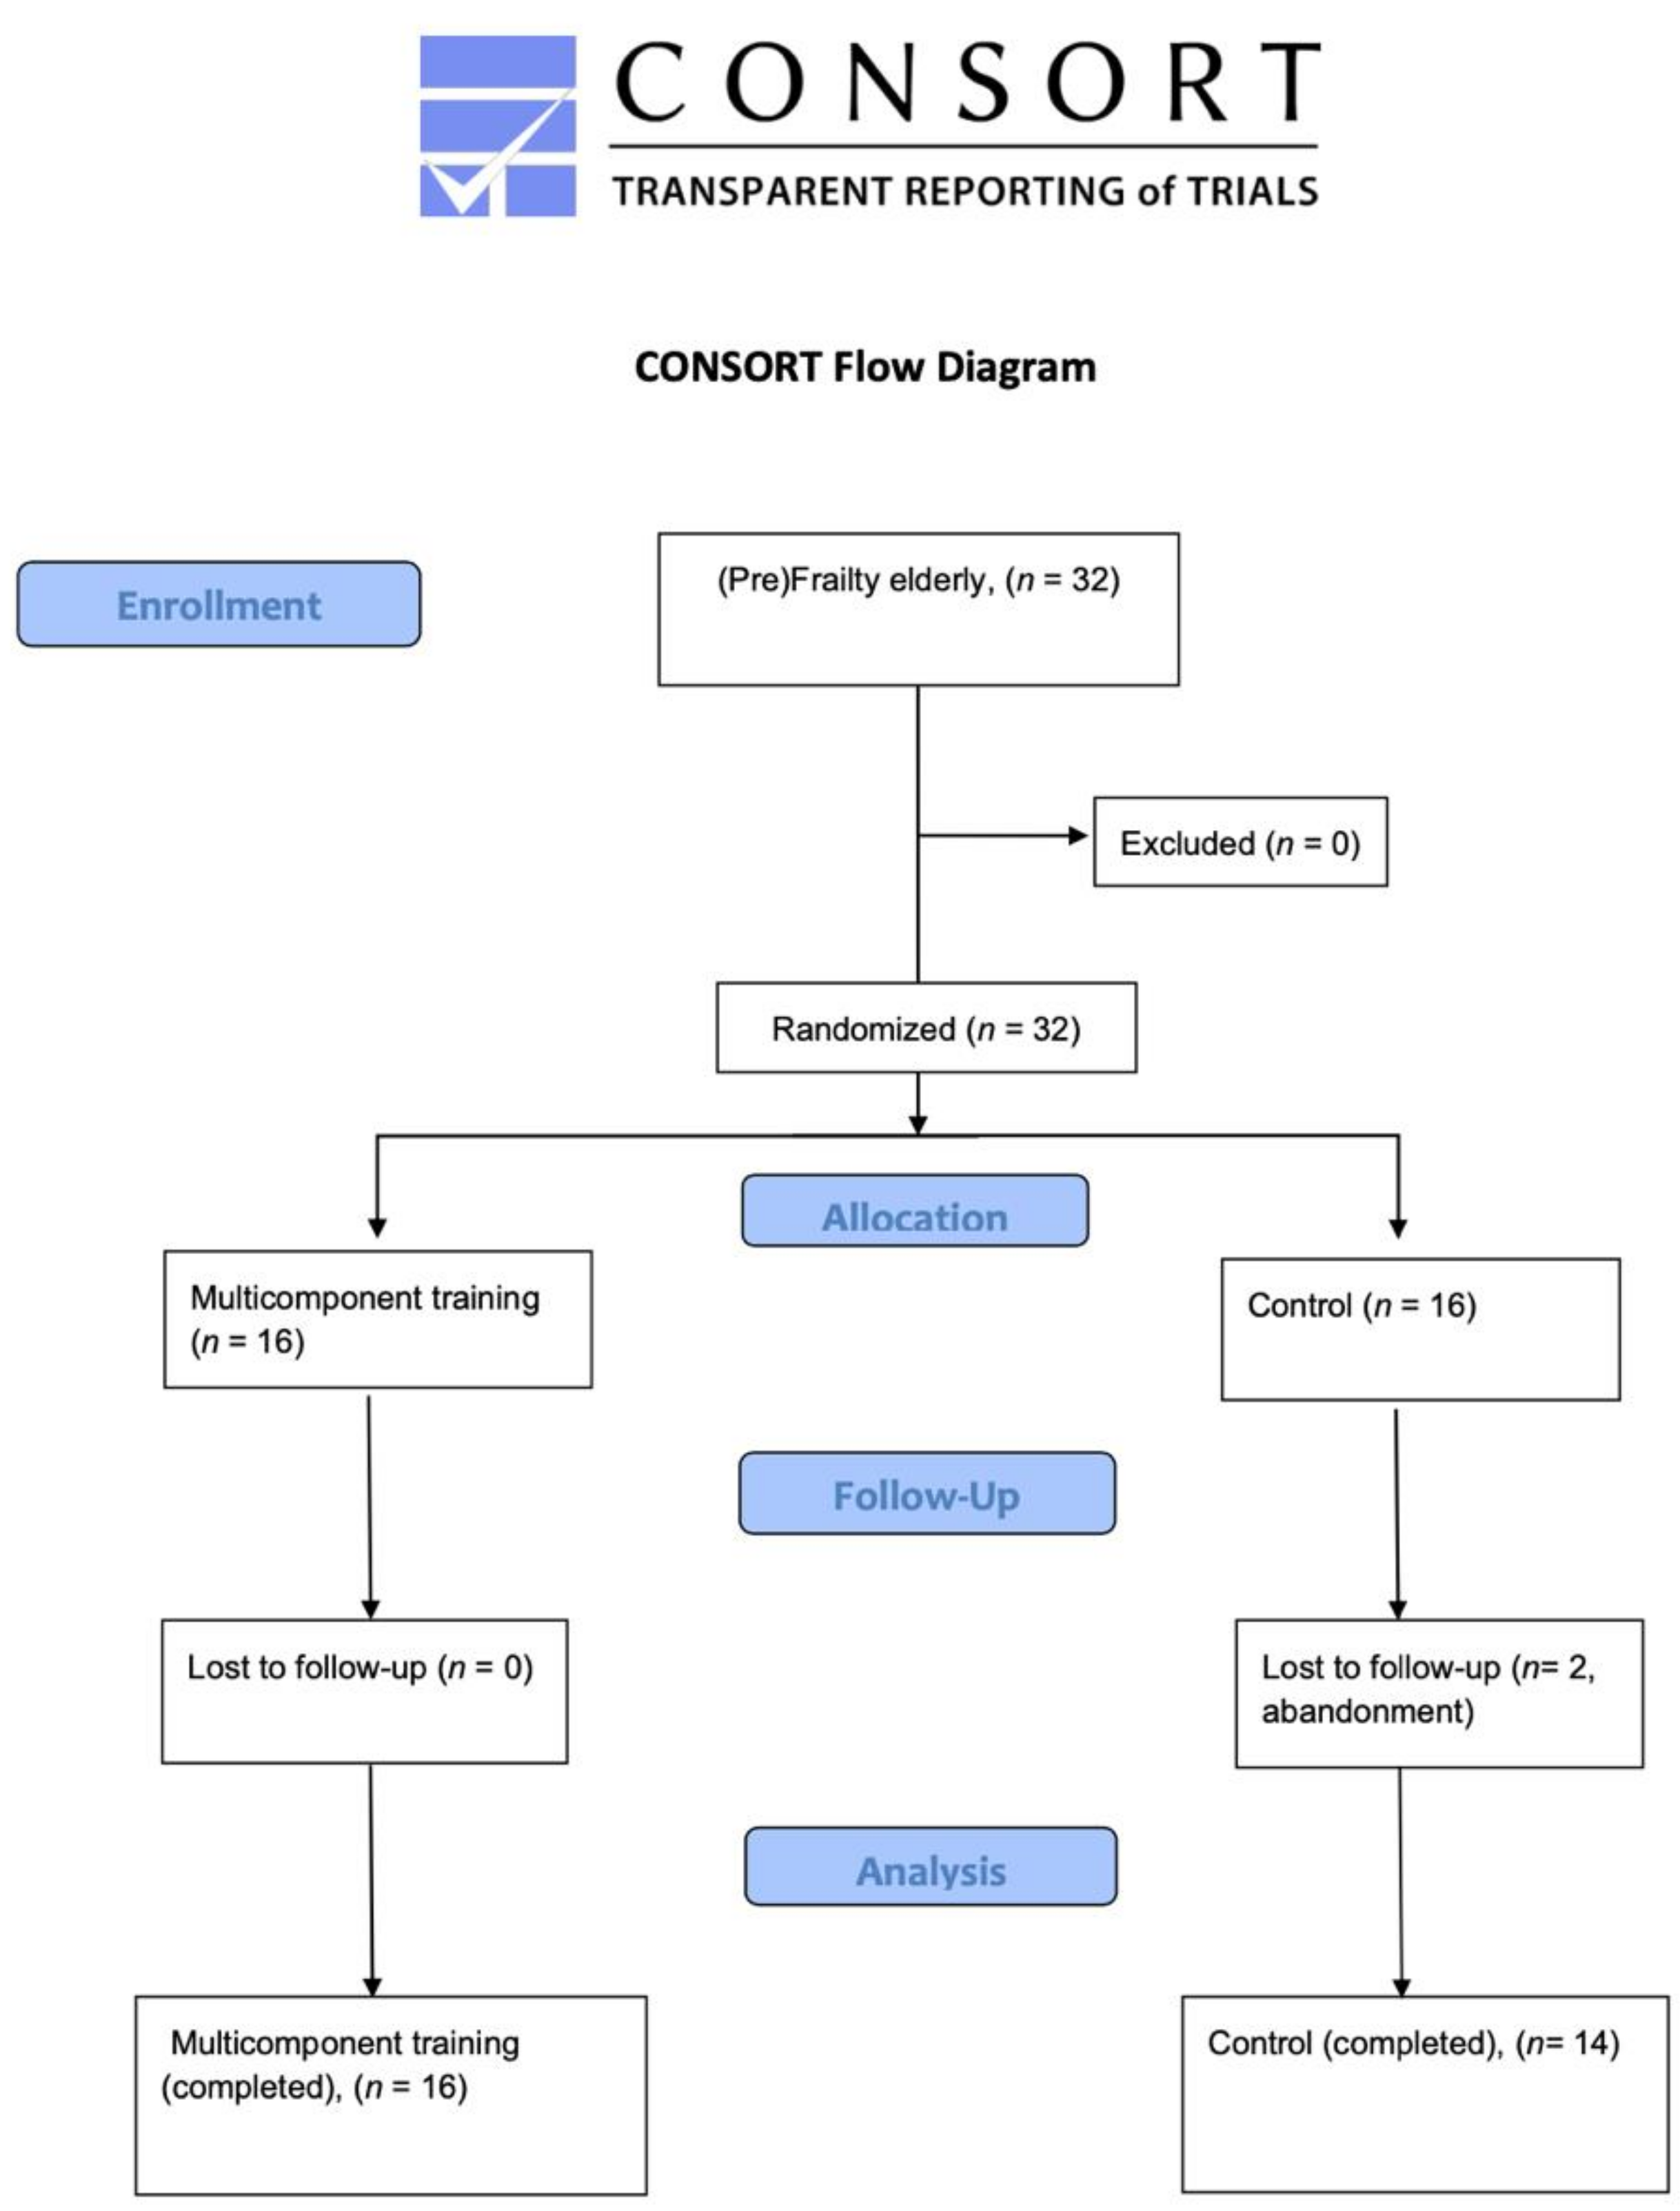

2.1. Study Design

2.5. Randomization